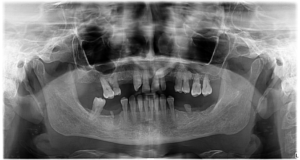

Am reușit să realizăm încă o transformare miraculoasă pentru pacienta noastră, care își dorea de mult un zâmbet perfect din punct de vedere estetic, dar mai ales funcțional.  Masticația este un proces important, ce are impact asupra sănătății generale. Atunci când aceasta nu poate fi realizată în mod corect, totul corpul are de suferit. Cum i-am redat sănătatea pacientei noastre?

• Am inserat 6 implanturi la maxilar și 6 la mandibulă

• Am folosit tehnica Sinus Lift – pentru a adăuga înălțime osului din jurul sinusurilor maxilare. Acest lucru a fost necesar deoarece am observat că în acea zonă era prezentă o insuficiență osoasă.